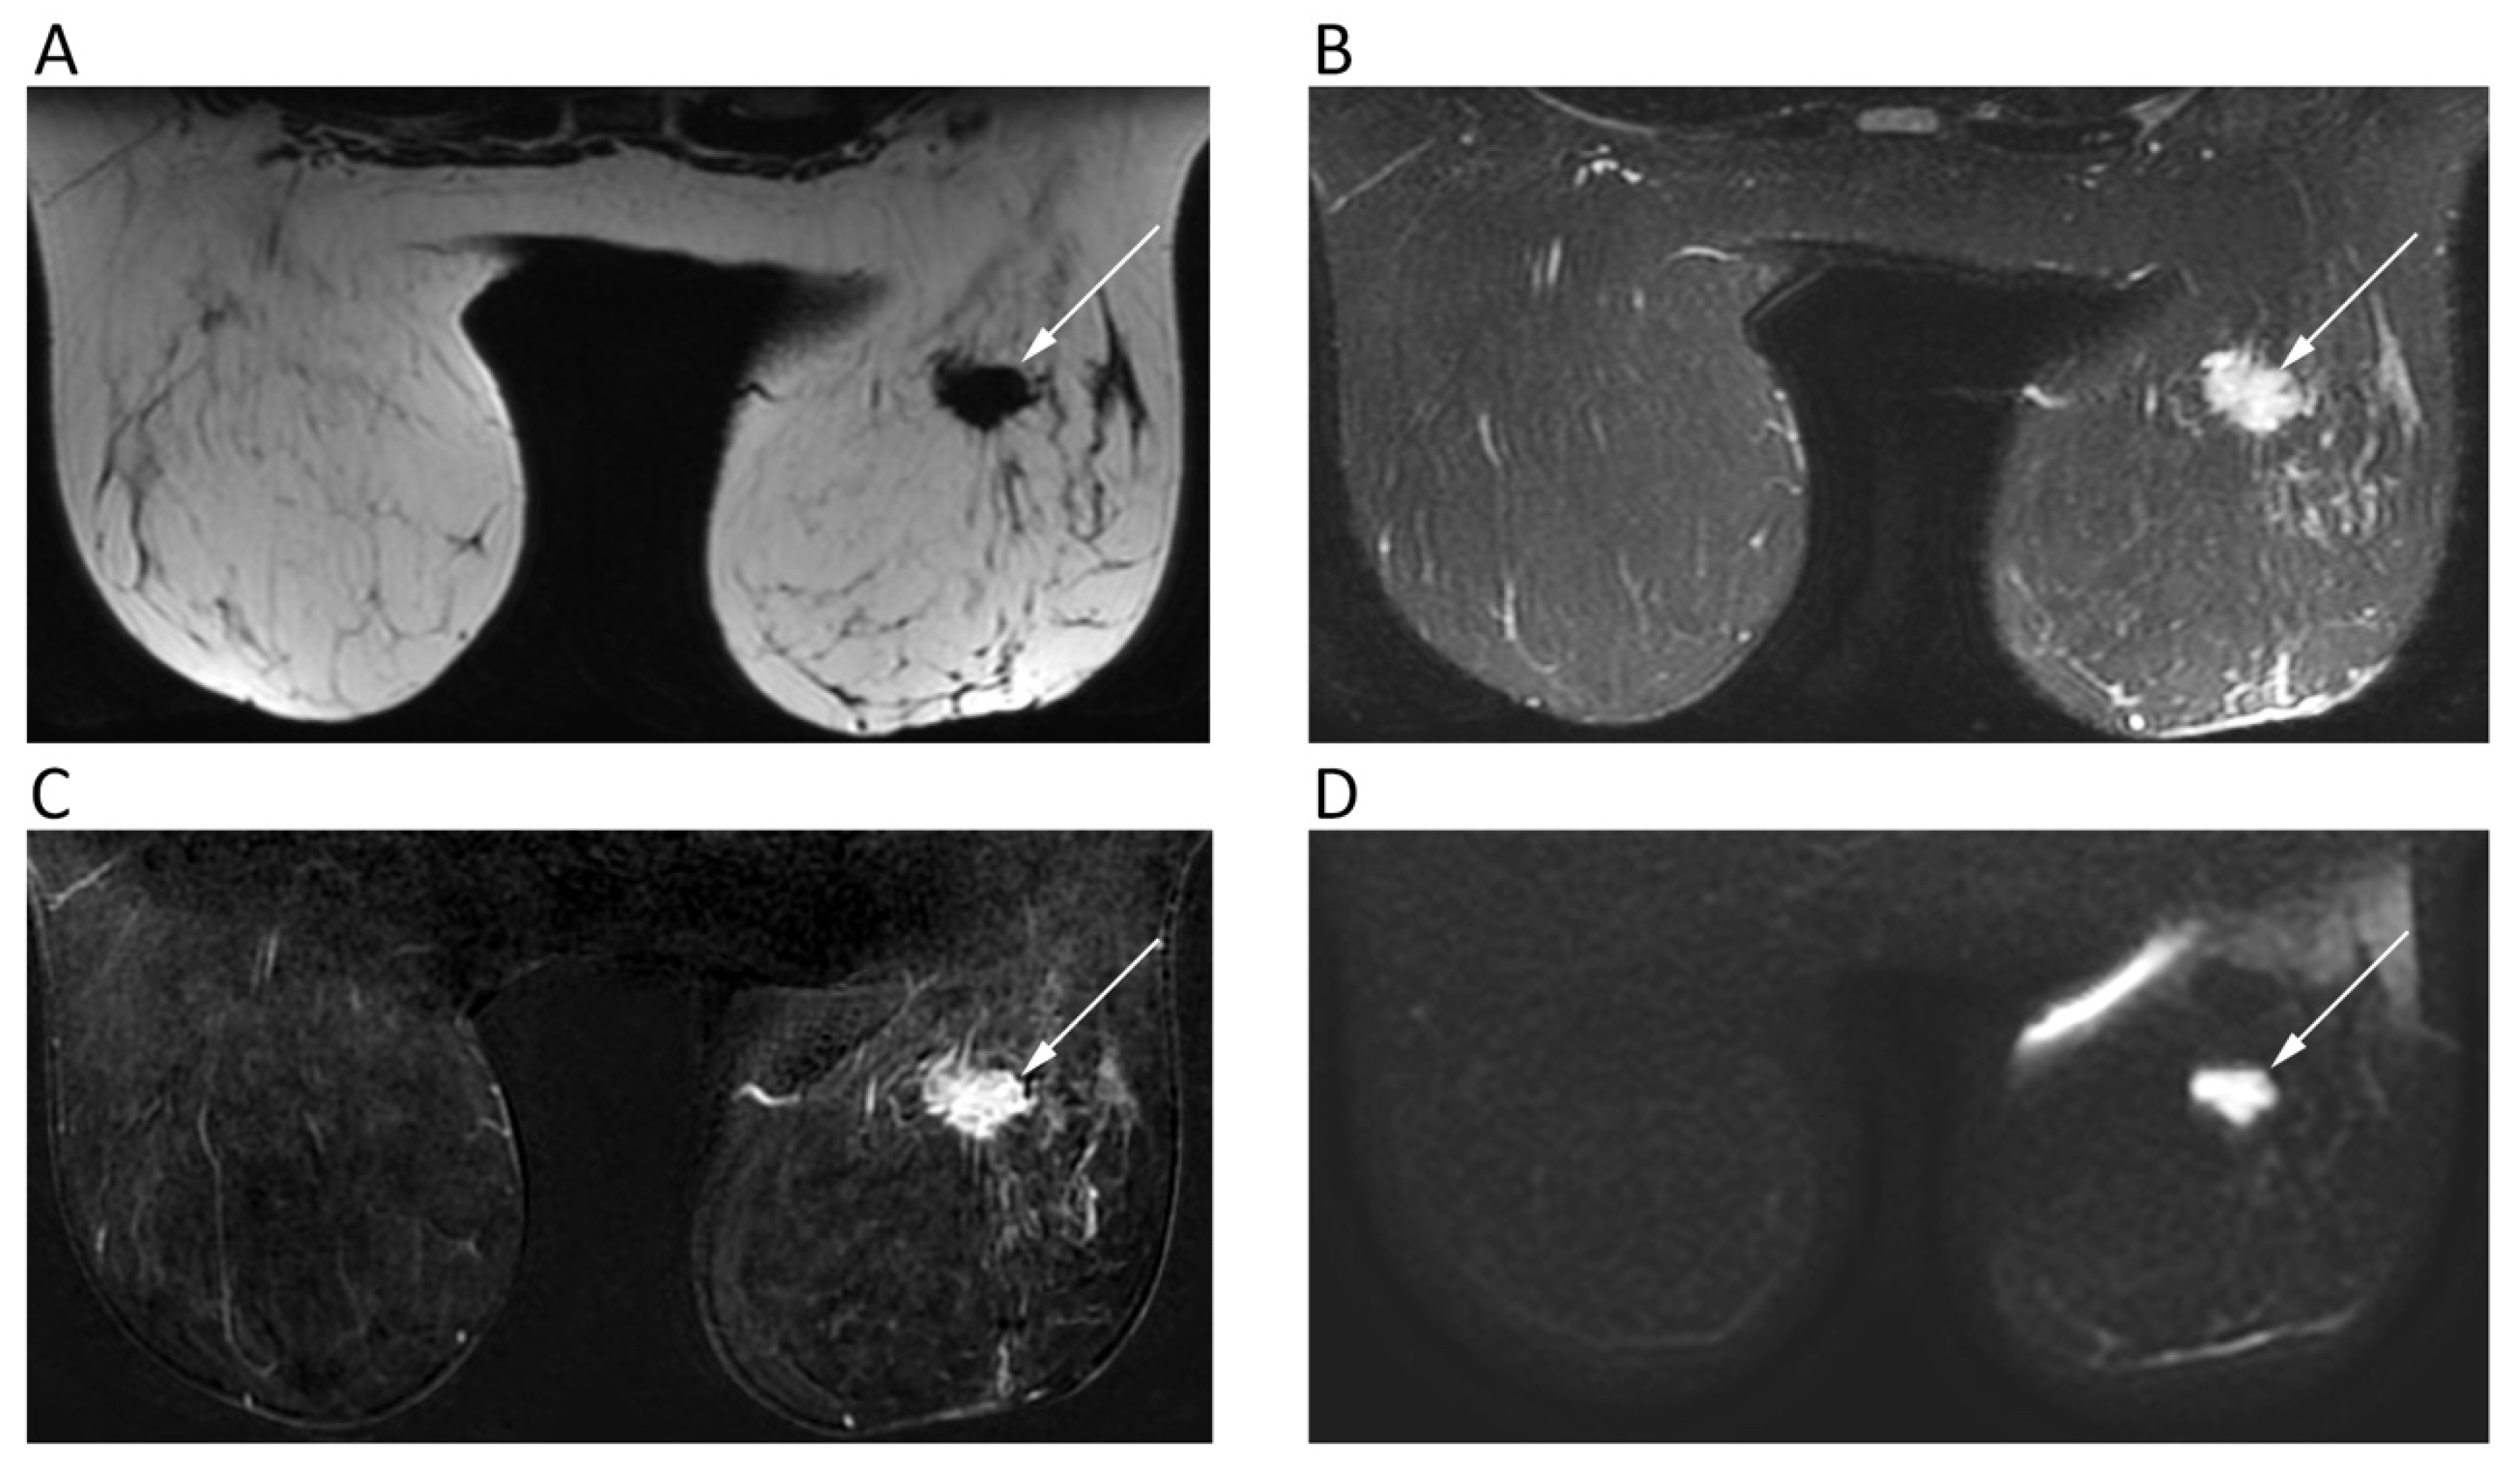

5. Breast

| Breast | Choi, S.Y.; et al. Br. J. Radiol. 2012 [25] | Retrospective; 335 patients with IDC NOS and DCIS; 1.5T MRI. | Mean ADC of IDC NOS (0.907 ± 0.160 × 10−3 mm2/s) was significantly lower than that of DCIS (1.113 ± 0.231 × 10−3 mm2/s). Mean ADC of ER-positive cancers was significantly lower than in ER-negative. |